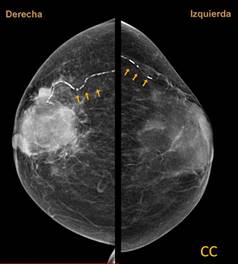

Se trata de paciente femenino de 74 años con antecedente de diabetes mellitus tipo 2. Acude a mastografía de tamizaje. Se aprecian dos proyecciones, densidad mamaria tipo B, con un nódulo irregular hiperdenso de márgenes espiculados de 5.1 × 5.2 cm en sus ejes mayores y se aprecian calcificaciones lineales (Figuras 1 y 2). Se otorga categoría BI-RADS 5.

Figura 1: Mastografía bilateral. Proyección cráneo-caudal, se observan calcificaciones lineales en patrón de “vía de ferrocarril” en cuadrantes externos.